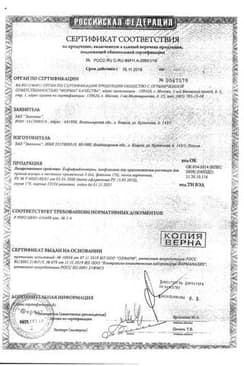

Сертификаты